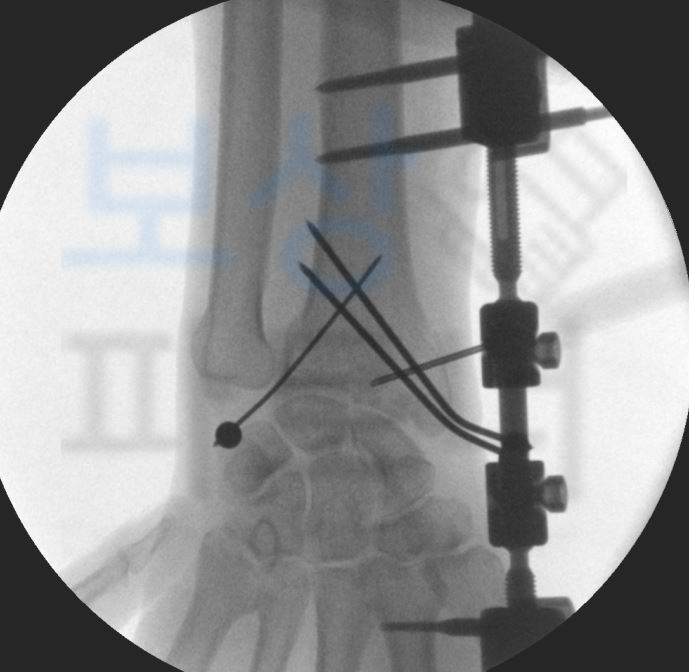

권@@님은 트럭을 정차해둔 상태에서 짐이 삐져 나와 있는 것을 발견하고 집어 넣으려다가 그대로 추락하는 사고를 당하셨습니다. 갑작스러운 사고로 인해 병원에 내원하여 정밀검사를 받아보니

요골 하단의 골절 과 함께 L1부위의 골절 즉 요추 1번의 척추압박골절 진단을 받으셨죠. 보존적 치료를 진행하여 척추뼈가 다 유합되어도 많은 분들이 수개월간 통증을 호소하시는데요, 개인적으로 가입하신 보험에서 보상 받을 수 있습니다.